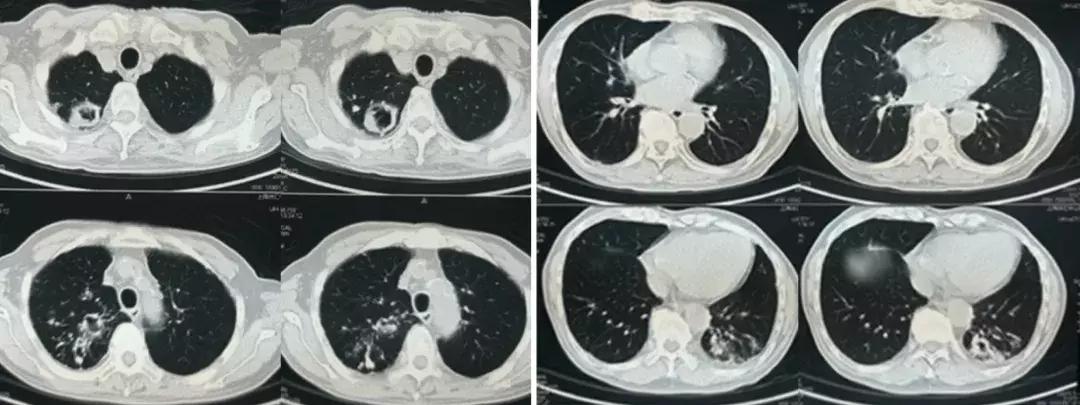

心电图:正常心电图;B超:胆囊显示不清,双侧胸腔积液(左侧见深约27mm无回声区,右侧见深约12mm无回声区,胰腺、脾脏、双肾未见明显异常。外院胸部CT(2018-7-19)示:右肺上叶及左肺下叶多发厚壁空洞,右肺上叶及两肺下叶炎症改变。(图1)

图1